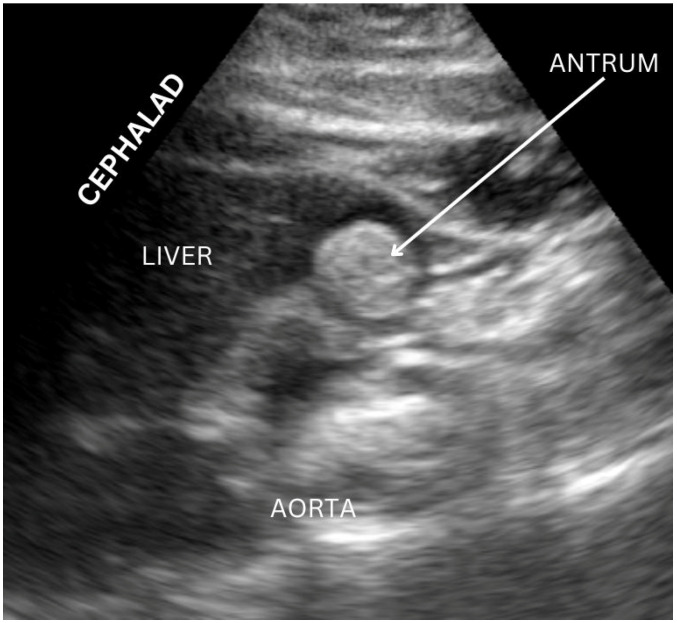

Once an appropriate patient has been identified, a standardized approach to performing gastric ultrasound can be followed, first with the patient in a supine position and then in the right lateral decubitus position (Figure 1). A curvilinear low-frequency probe is frequently used for adult patients, while a high-frequency probe may be more appropriate for pediatric patients [ref. 12]. The antrum has a reliable location, and, particularly in the right lateral decubitus position, it also has a more dependent location for gastric contents to gather while air is displaced laterally away from the sonographic beam [ref. 17]. The transducer is optimally placed in the midline under the xiphoid; at this location, the antrum is identified inferior to the left hepatic lobe and anterior to the retroperitoneal pancreas (Figure 2). An optimal view includes the abdominal aorta and superior mesenteric vessels which are distal to the antrum [ref. 18]. When empty, the antrum has been described as an ovoid shape with the anterior and posterior stomach walls in close proximity to one another; however, after ingestion of fluid, the antrum becomes distended with hypoechoic content, while after ingestion of solid food, the antrum may demonstrate a “frosted glass” appearance as artifacts from the interface between mucosa and air preclude the sonography of posterior structures [ref. 12,ref. 17,ref. 18].